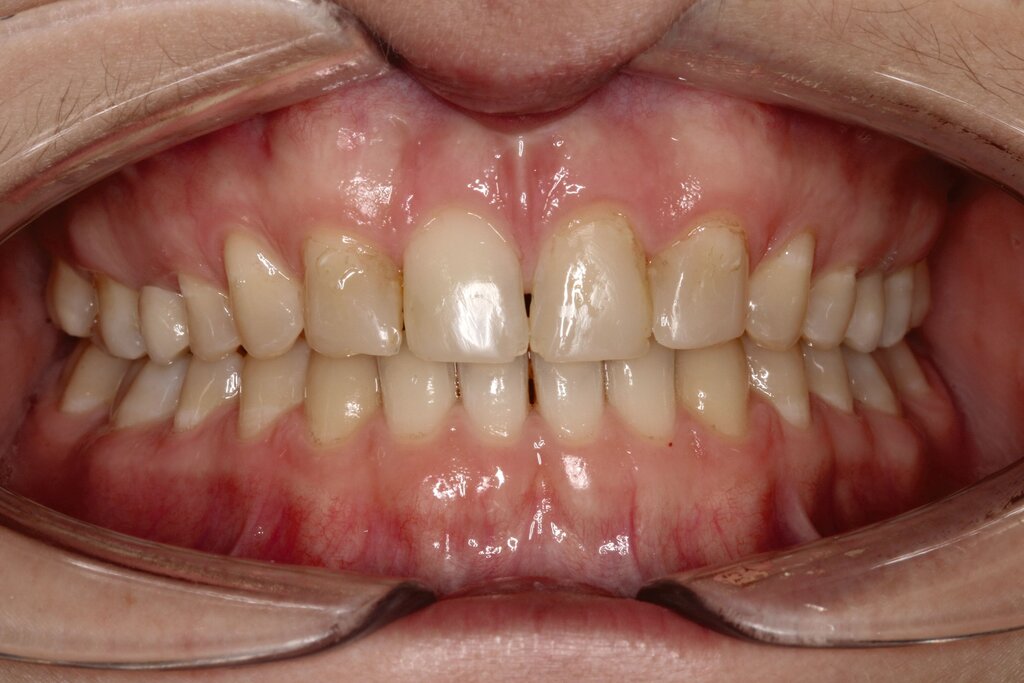

Bei dem gut zwölfjährigen Mädchen sind die seitlichen oberen Schneidezähne (Zähne 12 und 22) nicht angelegt. Zusätzlich zeigten sich verlagerte zweite obere Prämolaren.